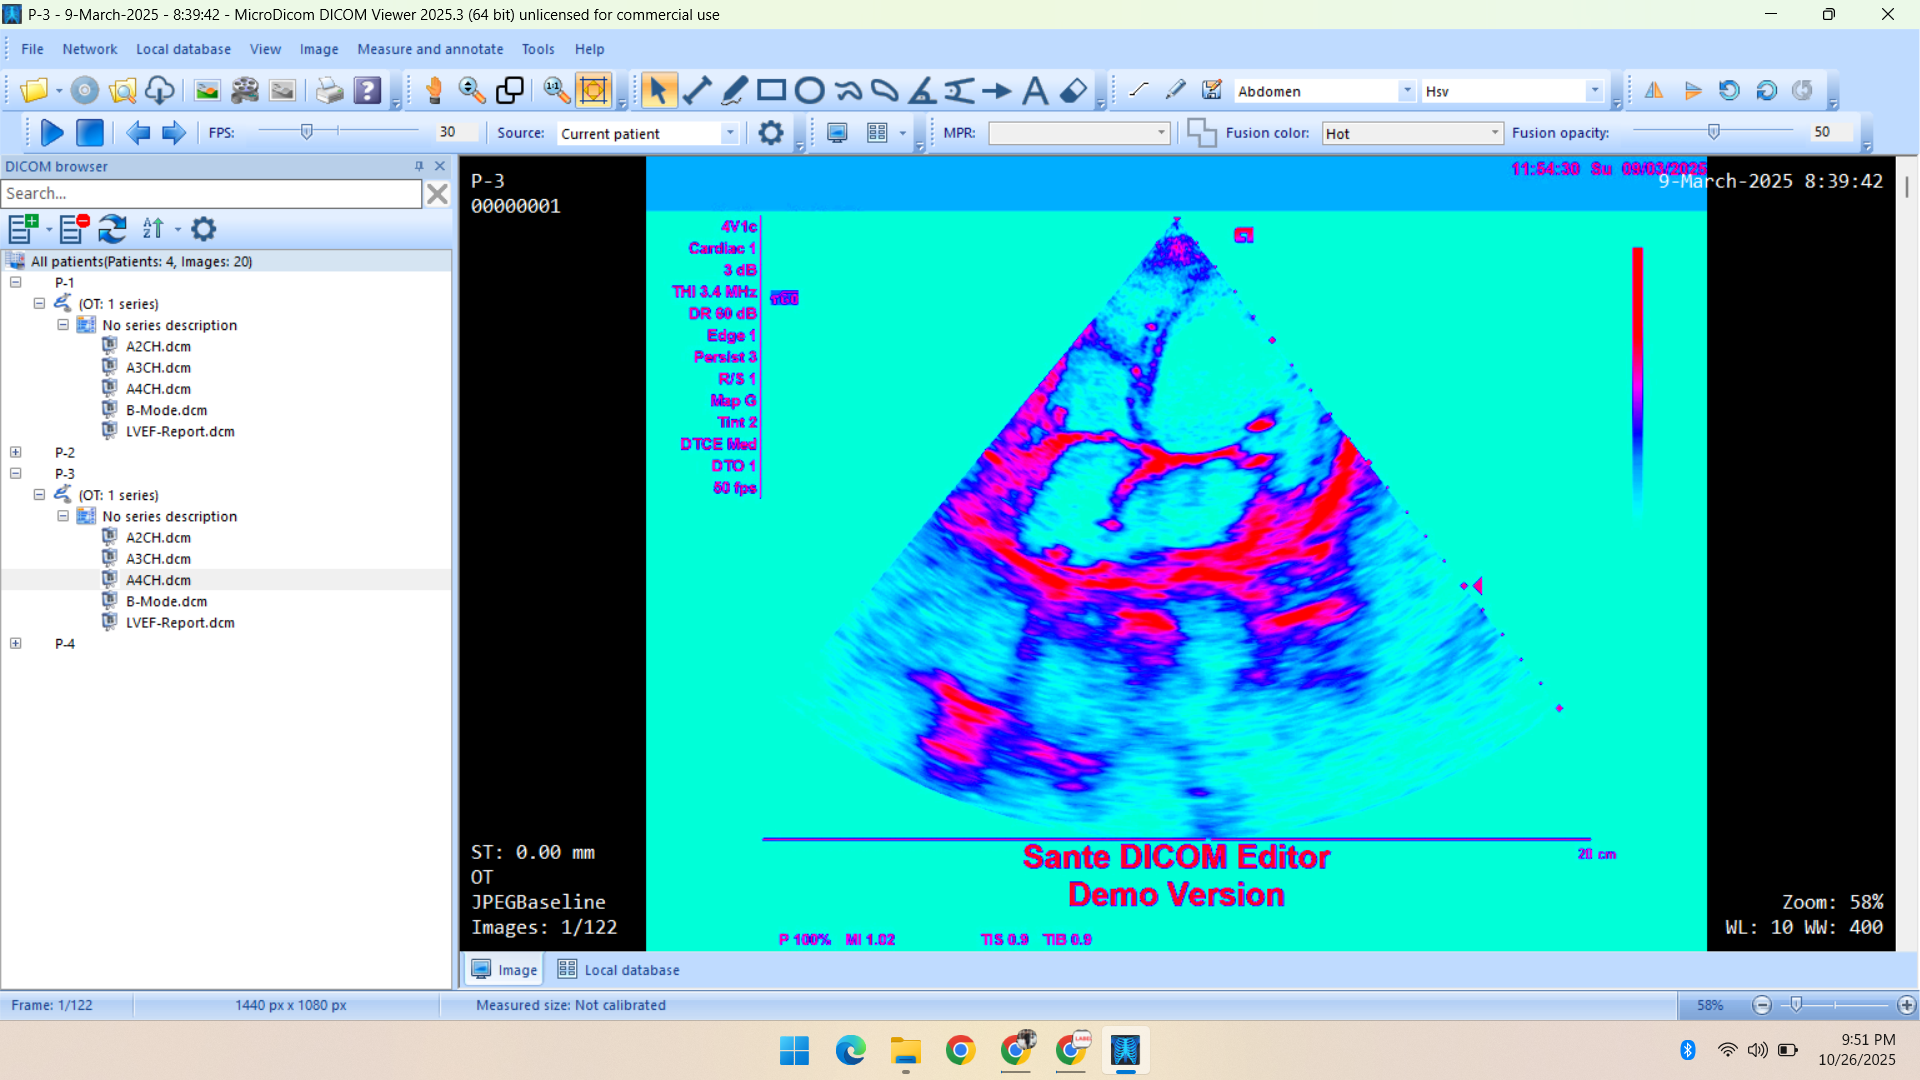

- Radiology Data – CT Scans, X-Rays, MRI, Echocardiography, Ultrasound.

Deep specialization in radiology, pathology, and histopathology datasets, annotated with medical precision.

Healthcare & Medical Data Supply

We specialize in healthcare datasets including radiology (CT, X-ray, MRI, Ultrasound, Echocardiography), pathology microscopy, and histopathology images — all ethically sourced and research-ready.

- Echocardiography